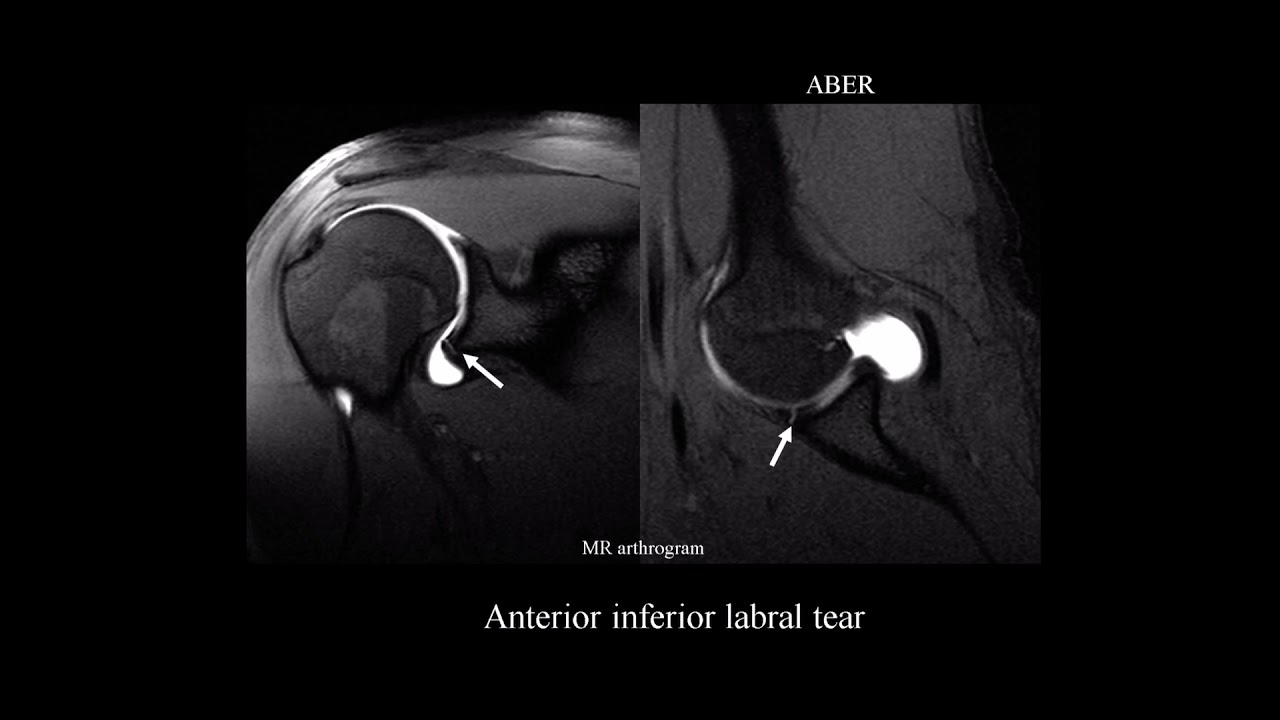

MRI shoulder labrum pathology

SSR REC - Unlocking the Complexities of the Glenohumeral Joint: Imaging the Labrum and Key Ligaments